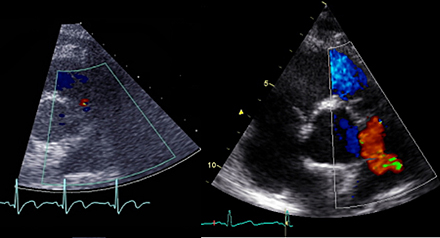

Missad förbindelse mellan aorta och lungartär. Bild: Kungliga tekniska högskolan

Ett exempel är vissa ultraljudsutrustningar som vid avbildningar av rörelser och strukturer i hjärtat kan visa så felaktiga bilder att läkarna riskerar att missa allvarliga diagnoser.